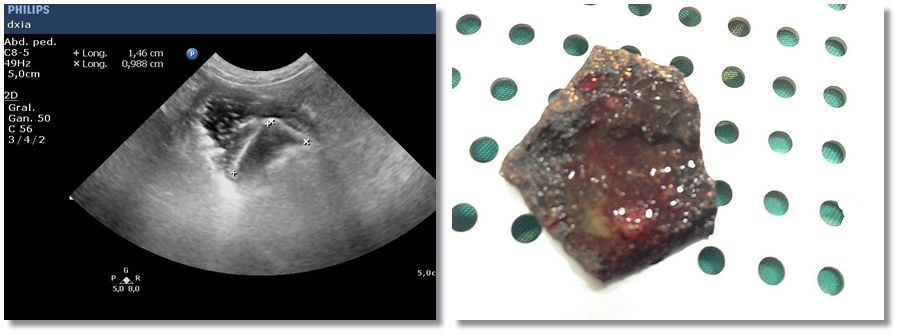

Cuerpo extraño/piedra

Paciente que acude con vómitos que no cesan con tratamiento médico, pérdida de peso y…